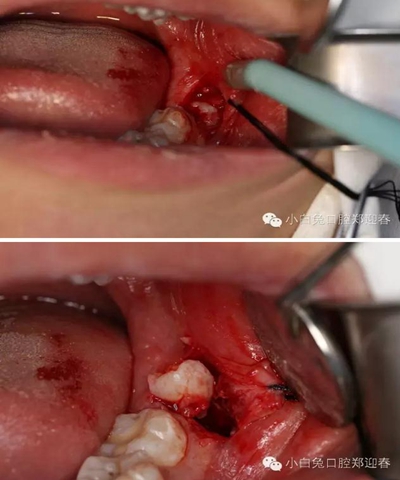

麻醉起效后,按照術前設計,行粘膜切開翻瓣。

切口勿偏舌側(cè),頰側(cè)不要越過前庭溝,避免術后腫脹。

為了防止渦輪高速手機可能的組織纏繞,利用縫合線牽拉切開的瓣膜,充分暴露術區(qū)。

利用微創(chuàng)拔牙標準進行阻力冠切割

切割過程對冷卻和角度的要求,一定要是水柱的噴射。

渦輪動力切割阻力牙冠

“T”型分割近中阻力冠

分別去除近中阻力冠的頰和舌部的牙冠

順著牙長軸的方向挺出牙根,這樣可以避免因為牙根旋轉(zhuǎn)對神經(jīng)管的影響。

處理牙槽窩,保留完整的牙槽骨形態(tài)。

置入膠原蛋白,縫合創(chuàng)口。